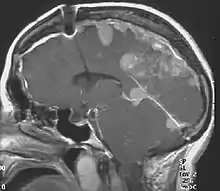

NF2 is a genetically transmitted condition. Diagnosis is most common in early adulthood (20–30 years); however, it can be diagnosed earlier. NF2 can be diagnosed due to the presence of a bilateral vestibular schwannoma, or an acoustic neuroma, which causes a hearing loss that may begin unilaterally.[15] If a patient does not meet this criterion of diagnosis, they must have a family history of NF2, and present with a unilateral vestibular schwannoma and other associated tumors (cranial meningioma, cranial nerve schwannoma, spinal meningioma, spinal ependymomas, peripheral nerve tumor, spinal schwannoma, subcutaneous tumor, skin plaque). This being said, more than half of all patients diagnosed with NF2 do not have a family history of the condition.[15] Although it has yet to be included into clinical classification, peripheral neuropathy, or damage to the peripheral nerves, which often causes weakness, numbness and pain in the hands and feet, may also lead to a diagnosis of NF2. In children, NF2 can present with similar symptoms, but generally causes "visual disturbances (cataracts, hamartomas), skin tumors, mononeuropathhy (facial paresis, drop foot), symptomatic spinal cord tumors, or non-vestibular intracranial tumors".[15]

Bilateral vestibular schwannomas are diagnostic of NF2.[16]

- Detection of bilateral acoustic neuroma by imaging-procedures

Meningiomas and schwannomas occur in around half of patients with NF2. Meningiomas are tumors that are both intracranial and intraspinal. Schwannomas are tumors that are often centered on the internal auditory canal. Patients with NF2 who have meningiomas have a higher risk of mortality, and the treatment can be very challenging. Individuals who develop schwannomas frequently develop hearing loss and deafness.[26] These individuals may also develop tinnitus after being presented with unilateral hearing loss. The first symptom that individuals may encounter is dizziness or imbalance.